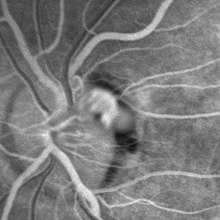

VHL "Free Floating" Juxtapapillary Hemangioblastoma

Jul 1 2014 by John S. King, MD

30-year-old female with fhx VHL and CNS hemangioblastomas and visceral lesions. P/C with a floater (no pvd or vh) after episodes of vomiting.

Photographer: Wayne A Ladlee Jr

Imaging device: FA 45 sec

Condition/keywords: retinal hemangioblastoma, Von Hippel-Lindau